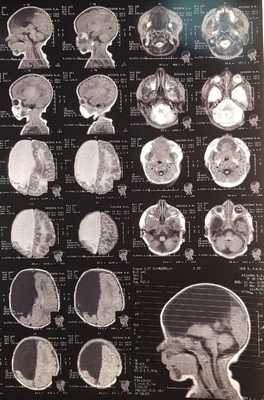

МРТ: на серии Т1- и Т2-взвешенных томограмм в сагиттальной и аксиальной проекции получено изображение супратенториальных структур головного мозга. Правые лобная, теменная и частично височная доли (кроме гиппокампа), мозолистое тело и прозрачная перегородка отсутствуют, нижний червь мозжечка гипопластичный. Правый зрительный бугор увеличен в размерах, визуализируется частично правая затылочная доля. Левое полушарие большого мозга, полушария мозжечка и ствол сформированы правильно. Ретенции желудочковой системы нет. Признаков объемного воздействия не отмечено. Базальные цистерны открыты. В заключении отмечено, что полученные данные могут соответствовать МР-картине семилобарной голопрозэнцефалии (рис. 2).

Так же пациенту Р. было проведено МРТ головного мозга: Заключение -полученные данные могут соответствовать МР-картине семилобарной голопрозэнцефалии.